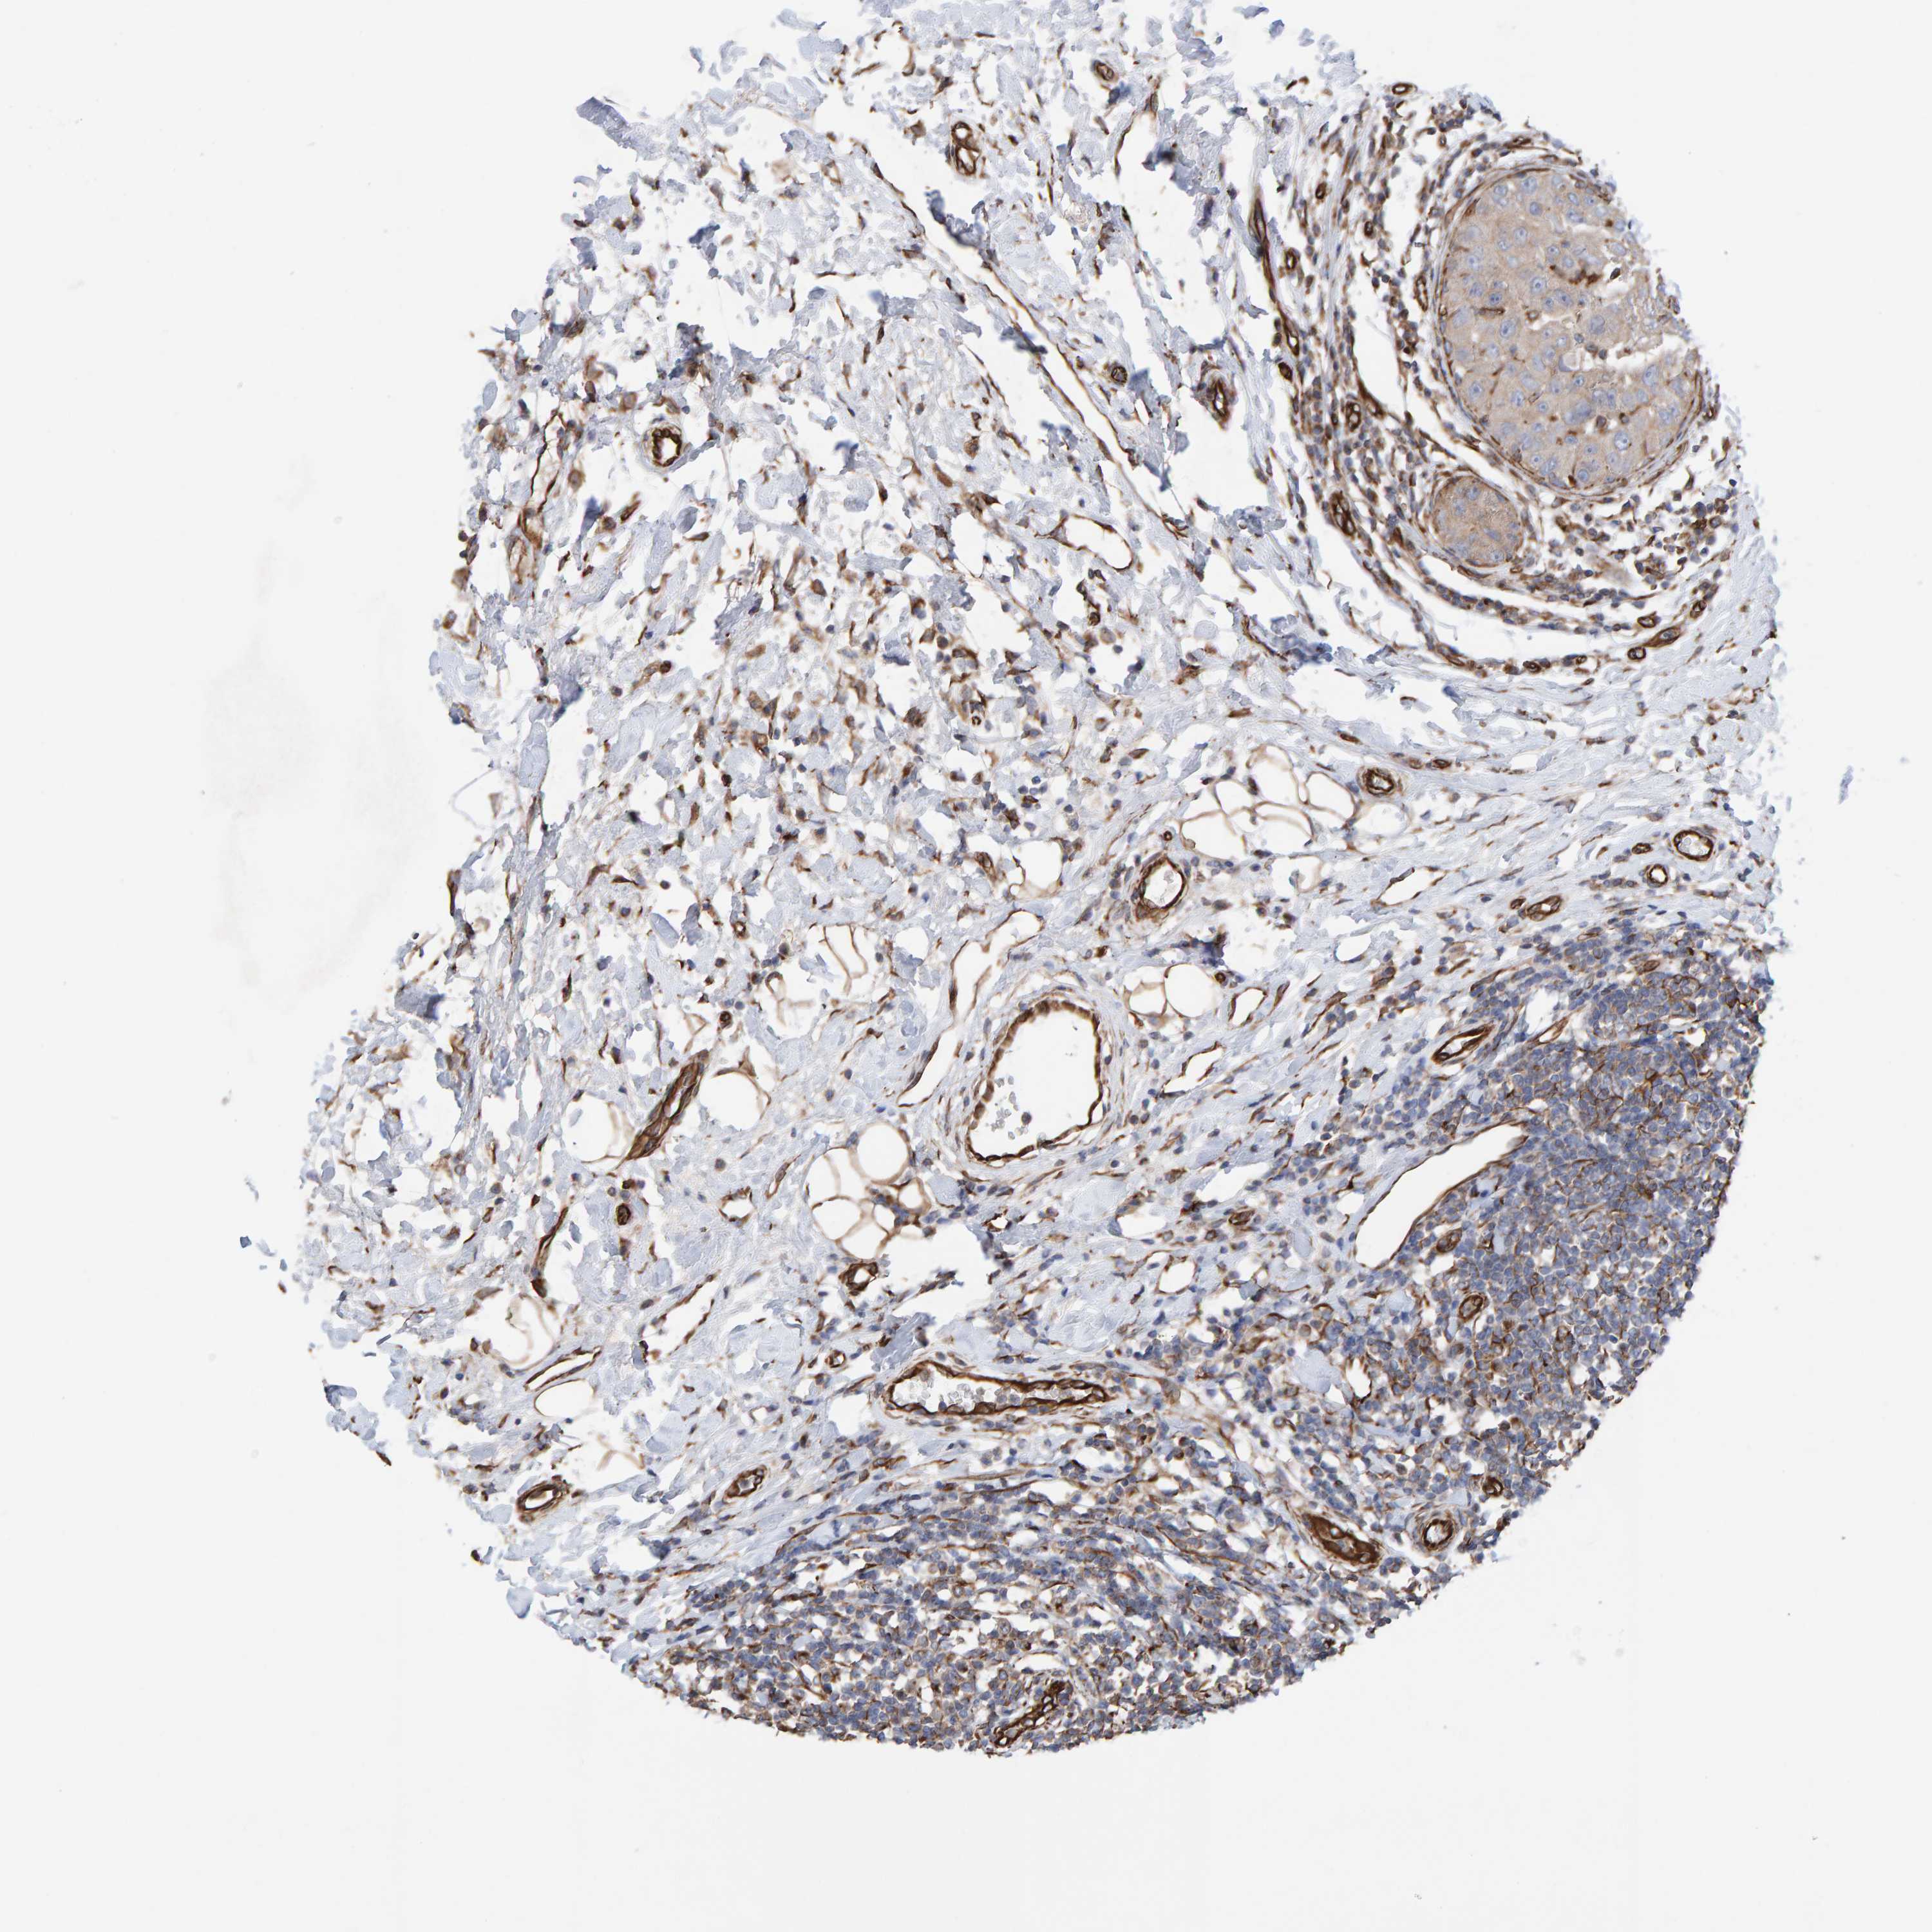

BRCA TCGA BRCA VALIDATION PROTEIN EXPRESSION

ANTIBODIES

AND

VALIDATION